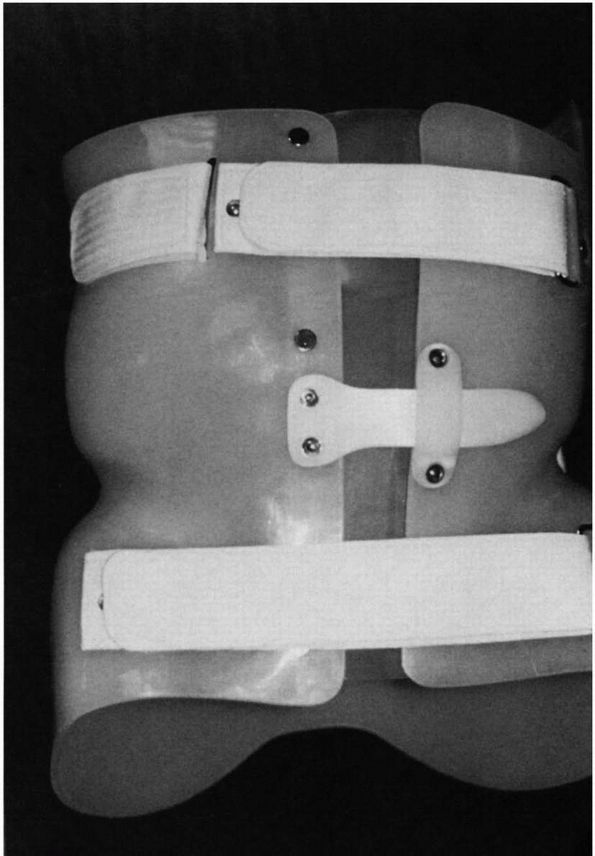

FIGURE 16-12. Milwaukee brace (CTLSO). The brace was developed in the late 1940s (A, frontal view of bone). Despite its widespread use, few long-term studies are available that evaluate the results of treatment (B,

view from behind with patient wearing brace). In addition, most studies fail to document curve progression; thus, it is uncertain whether those patients braced would have had continued progression had they not been braced. This type of brace was the “gold standard” for bracing but is rarely used today. It has been replaced by various models of underarm low profile braces such as seen in Figure 16-13. There are no published prospective controlled studies on bracing. |

physicians are choosing part-time bracing programs and using underarm

orthoses (Figure 16-13) because of compliance

problems. An underarm brace (thoracic-lumbar-sacral orthoses, TLSO) is

generally acceptable for use in curves with an apex of T8 or below.